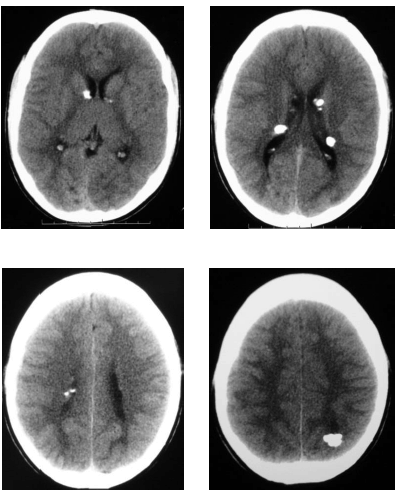

Paciente com 11 anos de idade, do sexo masculino, apresenta moderada deficiência intelectual e crises convulsivas, além de lesões cutâneas do tipo adenoma sebáceo, sem outras queixas ou outras patologias conhecidas. Realizou uma tomografia computadorizada cujas imagens são mostradas a seguir.

Em relação à patologia desse paciente, julgue o item a seguir.

O diagnóstico mais provável é da Síndrome de Sturge-Weber, sendo as calcificações subependimárias a sua manifestação de imagem mais típica na tomografia computadorizada.